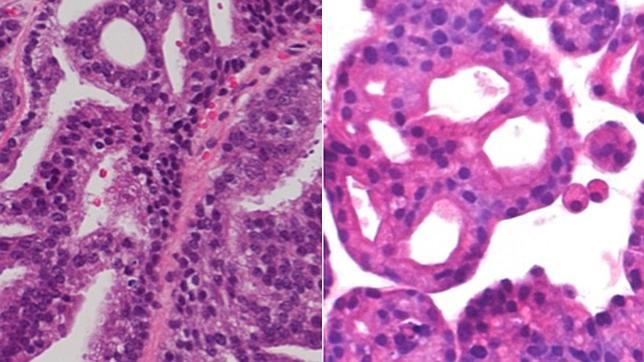

Los investigadores explican en el artículo que se publica en « Cell » que la estructura de los organoides es muy similar a la de las muestras de la metástasis de la que proceden. De hecho, la secuenciación de las muestras de metástasis y los organoides emparejados mostró que cada organoide es genéticamente idéntico al cáncer del paciente a partir del cual se originó.